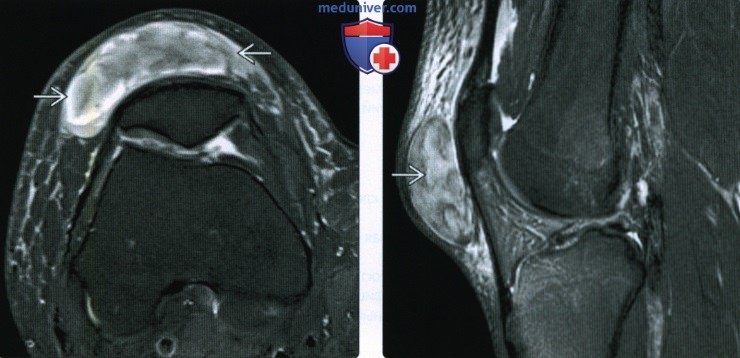

Заболевание сустава: симптомы и лечение